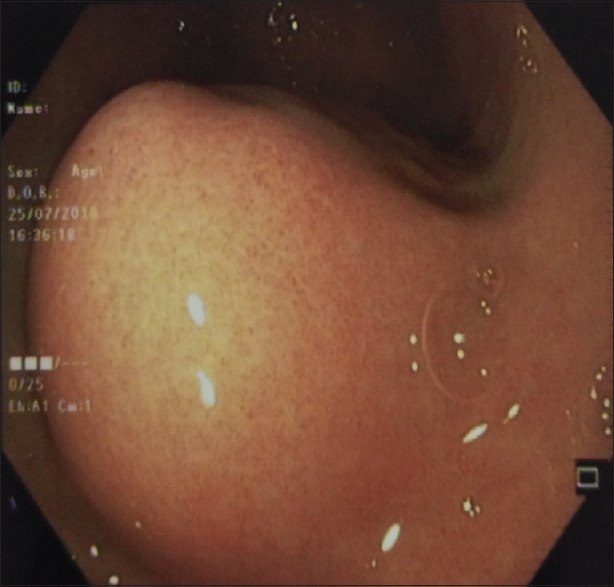

本病例报告描述了一种罕见的胃血管球瘤,它是一种间质起源的肿瘤。它们通常是良性的,占所有胃肠道软组织肿瘤的近1%。由于缺乏特异性特征,术前几乎无法诊断,常被误认为胃肠道间质瘤(gist)。在我们的医院设置,24岁的女性,表现为右腰腹痛,经过彻底的检查导致术前诊断为GIST,并进行远端胃切除术并Roux-en-y吻合。然而,术后病理和免疫组化检查结果与胃球囊瘤的诊断一致。在GIST-1 (DOG-1)上发现的无反应性可用于诊断肾小球瘤,有助于排除DOG-1阳性的GIST的诊断。因此,我们认为,基于免疫组织化学结果的鉴别诊断可以导致准确的术前诊断和进一步有针对性的手术干预。

This case report describes glomus tumor of the stomach, a rare entity, which is a mesenchymal origin tumor. They are generally benign and account for nearly 1% of all gastrointestinal (GI) soft-tissue tumors. They are almost impossible to diagnose preoperatively because of the lack of specific characteristics and are often mistaken for GI stromal tumors (GISTs). In our hospital setup, a female aged 24 years, presented with right lumbar abdominal pain which after a thorough workup leads to the preoperative diagnosis of GIST, and distal gastrectomy with Roux-en-y anastomosis was done. However, pathological and immunohistochemical findings done after the surgery were found consistent with the diagnosis of gastric glomus tumor. Discovered on GIST-1 (DOG-1) nonreactivity is considered for the diagnosis of glomus tumor which helps in excluding the diagnosis of GIST, which is positive for DOG-1. Hence, it was concluded that differential diagnosis on the basis of immunohistochemical findings can lead to an accurate preoperative diagnosis and further targeted surgical intervention.